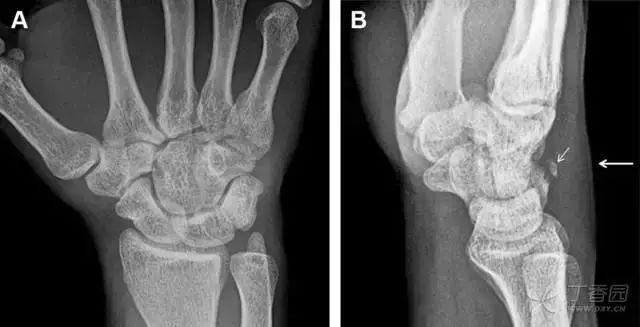

舟状骨骨折

舟状骨骨折 60%~70% 发生于腰部,15% 发生于近极, 10% 发生于远极, 8% 发生于远端关节面。除了常规的前后位、侧位、斜位片外,还需要拍专门的舟状骨位片(腕关节尺偏,以舟状骨为中心的腕关节前后位片),特别是鼻烟壶有压痛时。

图 2 舟状骨骨折 (A、B)第 1 例患者,舟状骨远极关节内骨折(白色箭头),斜位片显示较清楚(B);(C、D)第 2 例患者,舟状骨腰部骨折(虚线箭头),斜位片显示较清楚(D);(E~H)第 3 例患者,舟状骨近极骨折,常规 X 线片均未看到骨折,而在舟状骨位片上才能见到骨折(虚线圆)。